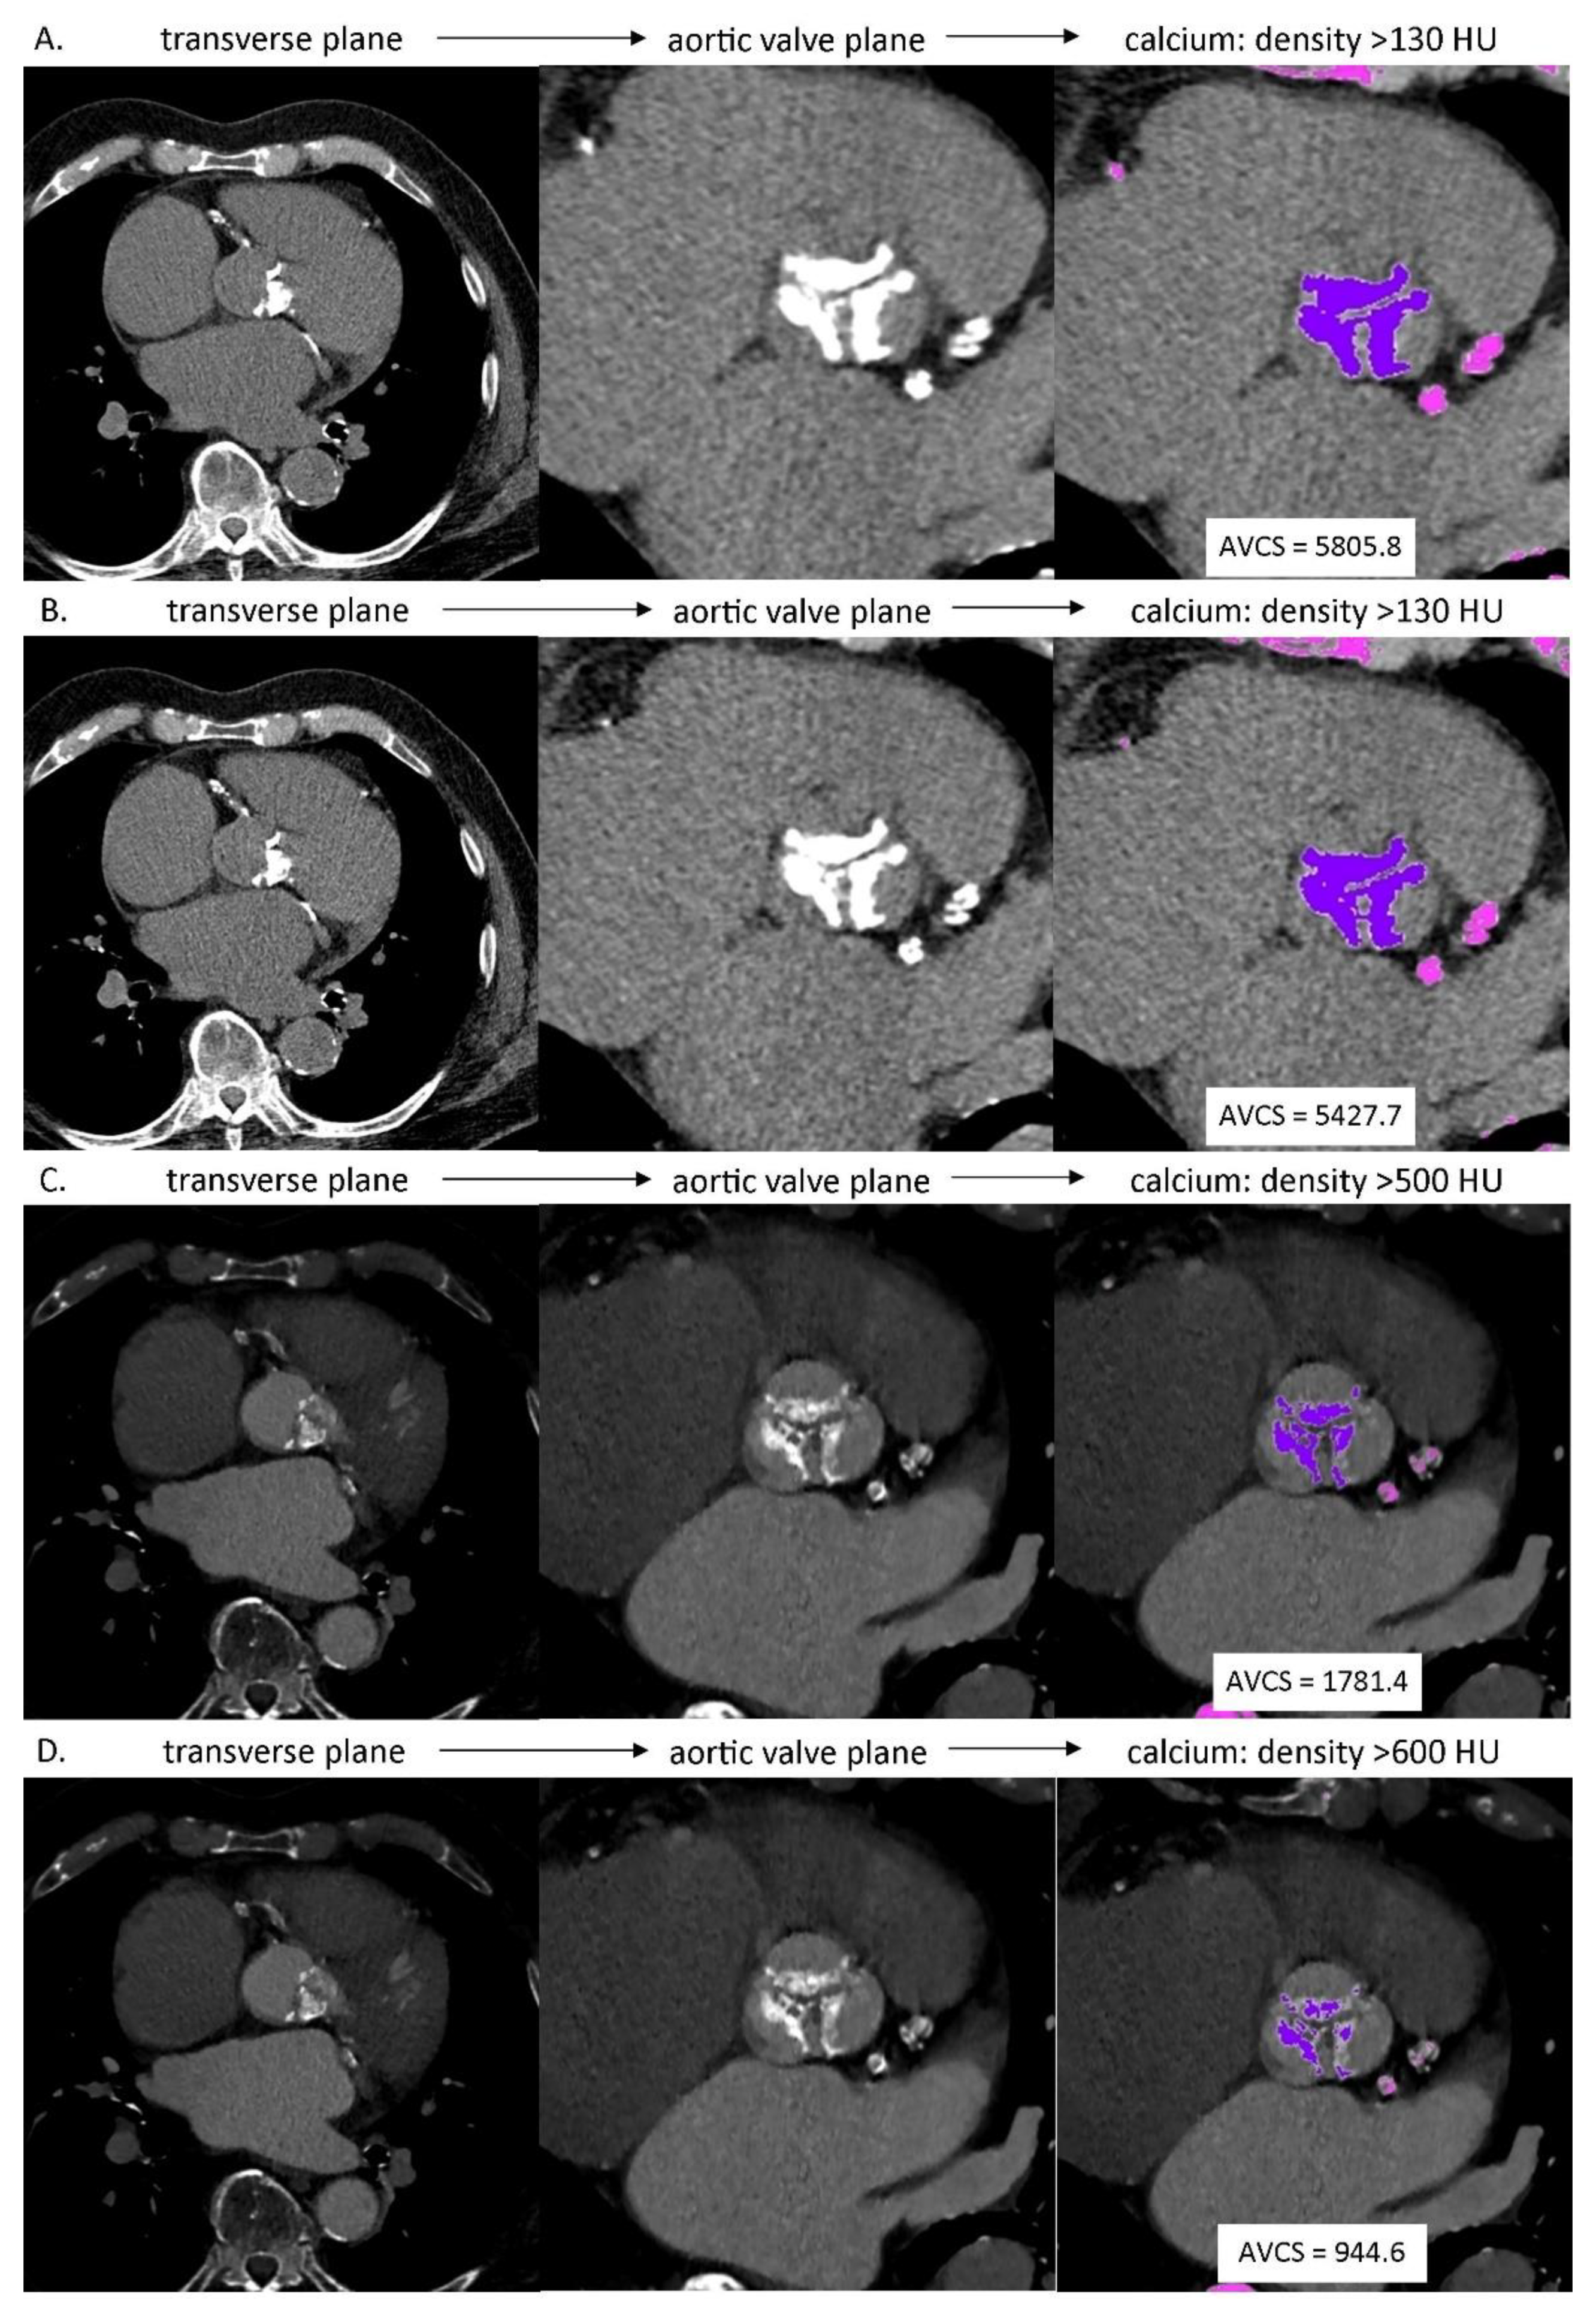

2.2.3. Evaluation of Aortic Valve Calcium Score